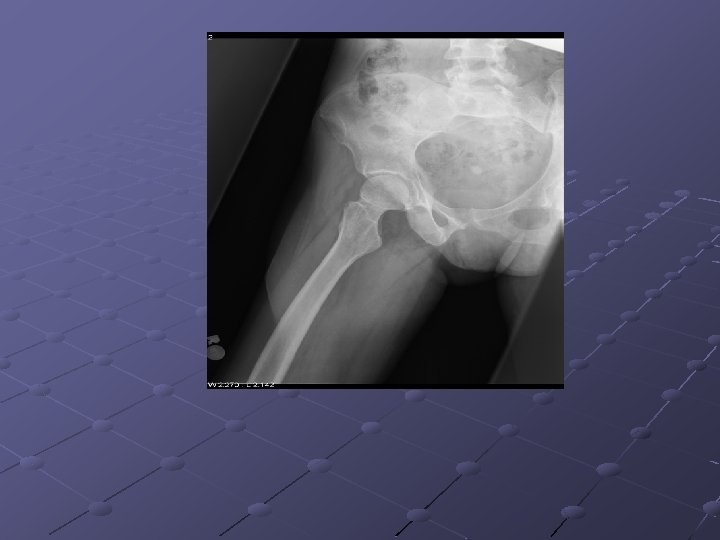

Imaging Studies